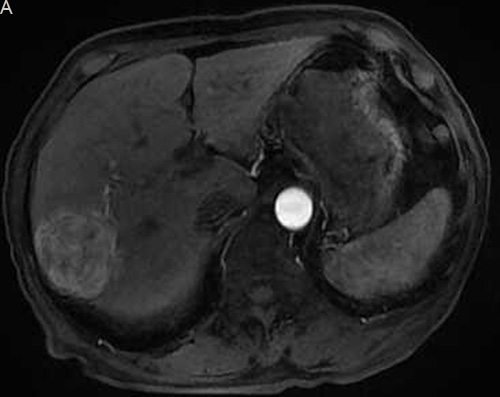

Figure 2: Eighty six-year-old male with a huge hypervascular metastatic pancreatic neuroendocrine tumor treated with multiple cycles of chemotherapy. A. Gd-enhanced T1WI revealed a round enhanced tumor of the right lobe in the arterial phase. B. Tumor staining during arterial phase of DSA: The tumor was nourished by the branches of the right hepatic artery. C. Tumor staining disappeared after TACE therapy. D. Gd-enhanced T1WI 2 image months after drug-eluting microspheres loaded with oxaliplatin chemoembolization showed signal reduction indicating resorption without enhancing residual or recurrent tumor mass.